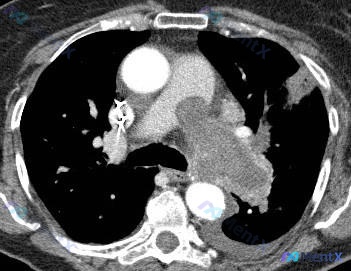

- 影像:胸部CT纵隔窗横断面(主动脉弓下至肺门水平),发现中纵隔隆突下及左肺门区团块状软组织密度影,有分叶,密度较均匀,未见明显钙化/脂肪/坏死,与左主支气管、左肺动脉关系密切,有推挤/包绕趋势,占位效应明显

目前影像提示的鉴别方向大概有:

- 转移性淋巴结肿大(比如肺癌转移)

- 淋巴瘤

- 肉芽肿性病变(比如结核)

📋答案:优先推荐FDG-PET/CT作为下一步检查;待PET/CT明确代谢活性与全身情况后,再行EBUS-TBNA等靶向活检;同时可完善LDH、肿瘤标志物、T-SPOT.TB等实验室检查。